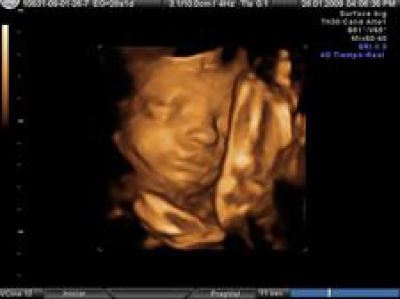

Hay cosas que suceden todos los días y, por ello, no son noticia, pero deberían serlo. Hoy se acabará con la vida de unos doscientos mil niños no nacidos, con el beneplácito de gobiernos, parlamentos, médicos e incluso de sus padres. https://www.infocatolica.com/?t=noticia&cod=52974